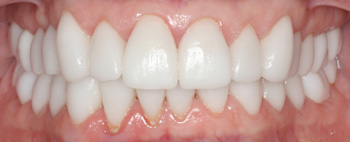

Clinical Cases